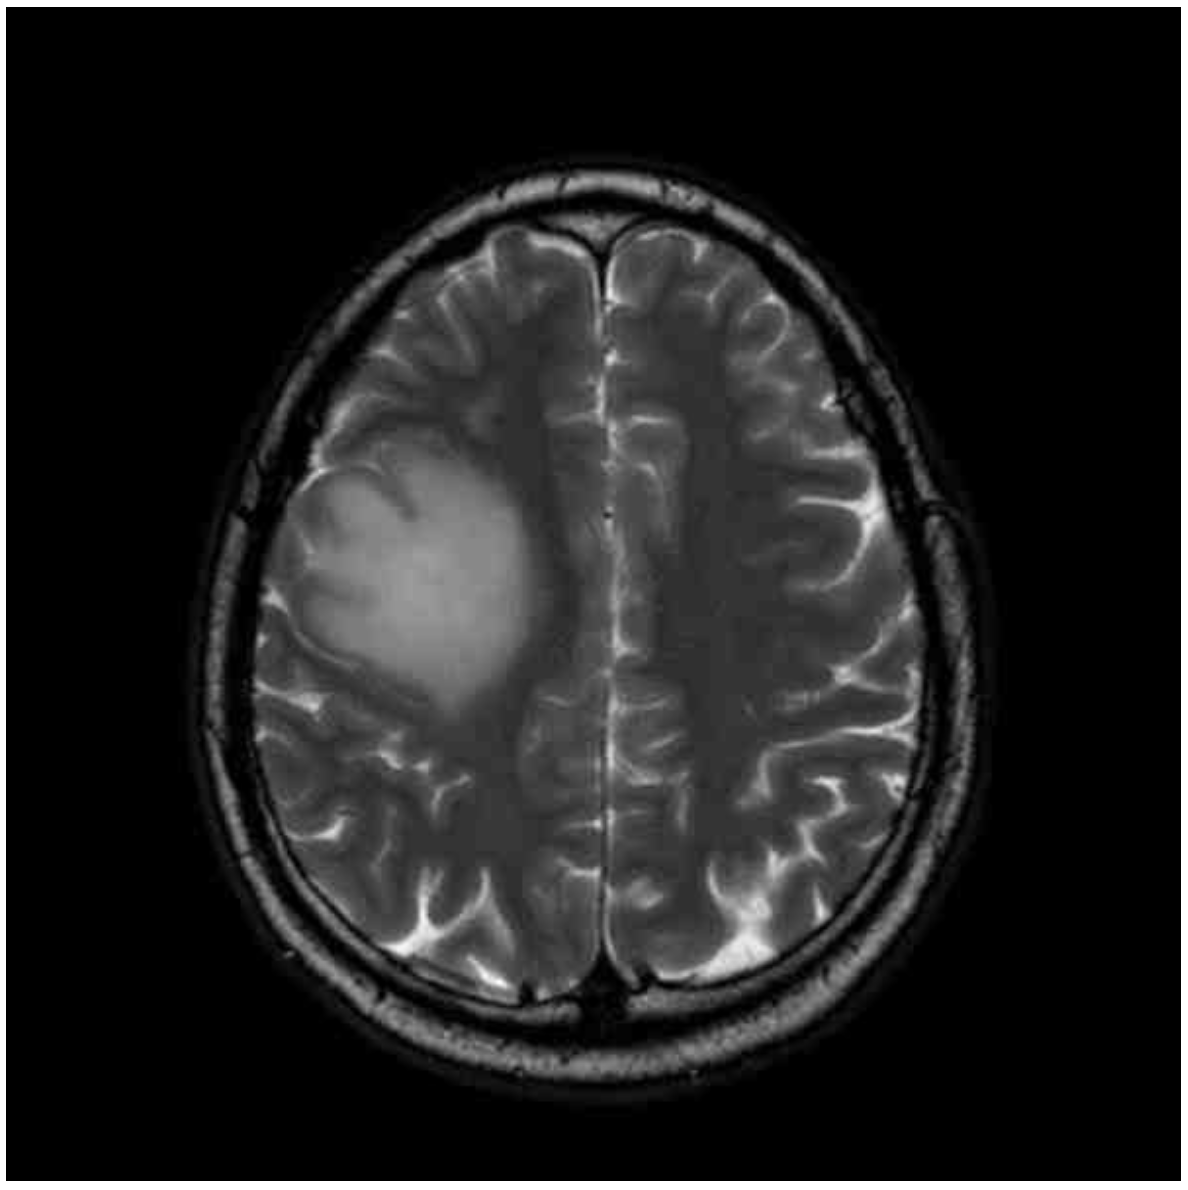

Img | MRI: T1WI hypointense, T2WI hyperintense Rt. frontoparietal mass |

T2-weighted brain MRI에서 hyperintense mass, T1-weighted brain MRI에서 hypointense mass가 확인되므로 뇌종양으로 진단한다.

• 뇌 영상검사 상 T2-weighted brain MRI에서 hyperintense mass, T1-weighted brain MRI에서 hypointense mass가 확인되므로 뇌종양으로 진단한다.

② T2WI: 고음영 종양 (물 고음영, 지방 저음영)